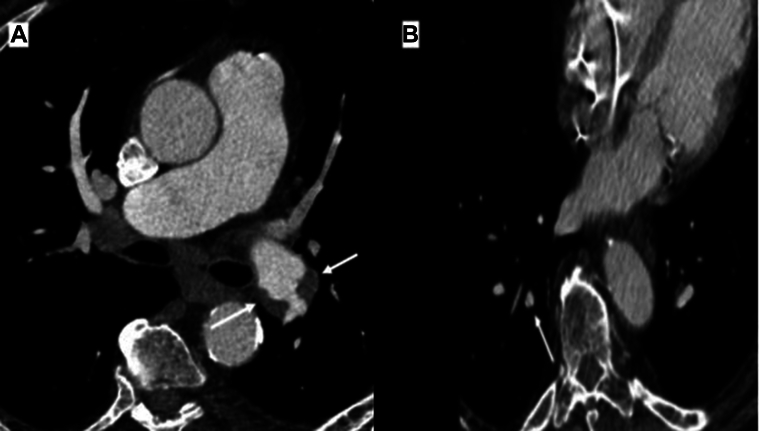

Balloon pulmonary angioplasty (BPA) is an evolving treatment modality for patients with chronic thromboembolic pulmonary hypertension (CTEPH) who are not candidates for pulmonary endarterectomy. Although several imaging modalities currently exist for evaluating CTEPH, their individual use, specifically in the clinical practice of BPA, has not been well described. In this article, we provide a preprocedural, intraprocedural, and postprocedural interventional imaging roadmap for safe and effective BPA performance in routine clinical practice. Preprocedural assessment includes transthoracic echocardiography for right ventricular assessment, ventilation/perfusion scan to identify pulmonary segments with the highest degree of hypoperfusion, cross-sectional chest imaging excluding alternative causes of mismatched defects and providing anatomic and perfusion imaging concurrently, and nonselective invasive pulmonary angiography for risk stratification of individual lesion subtypes. Intraprocedural assessment includes subselective segmental angiography (SSA) for delineating segmental and subsegmental branch anatomy, lesion identification, and vessel sizing. Intravascular ultrasound and optical coherence tomography serve as adjunctive intraprocedural tools for more accurate vessel sizing and lesion characterization when SSA alone is insufficient. Postprocedural considerations include chest radiography to monitor for immediate postprocedure complications and echocardiography for the interval assessment of the right ventricle on longer-term follow-up.

对于不适合进行肺动脉内膜切除术的慢性血栓栓塞性肺动脉高压(CTEPH)患者来说,球囊肺血管成形术(BPA)是一种不断发展的治疗方式。虽然目前有多种成像模式可用于评估 CTEPH,但它们各自的用途,特别是在 BPA 临床实践中的用途,还没有得到很好的描述。在本文中,我们为常规临床实践中安全有效地实施 BPA 提供了一个术前、术中和术后介入成像路线图。术前评估包括用于评估右心室的经胸超声心动图、通气/灌注扫描以确定灌注不足程度最高的肺段、横断面胸部成像以排除造成不匹配缺损的其他原因并同时提供解剖和灌注成像,以及用于对个别病变亚型进行风险分层的非选择性有创肺动脉造影。术中评估包括亚选择性节段血管造影术(SSA),用于划分节段和亚节段分支解剖结构、病变识别和血管大小。血管内超声和光学相干断层扫描可作为术中的辅助工具,在单靠亚选择节段血管造影不足以确定血管大小和病变特征时,可用于更准确地确定血管大小和病变特征。术后注意事项包括胸片检查,以监测术后即刻出现的并发症,以及超声心动图检查,以便在长期随访中对右心室进行间隔评估。